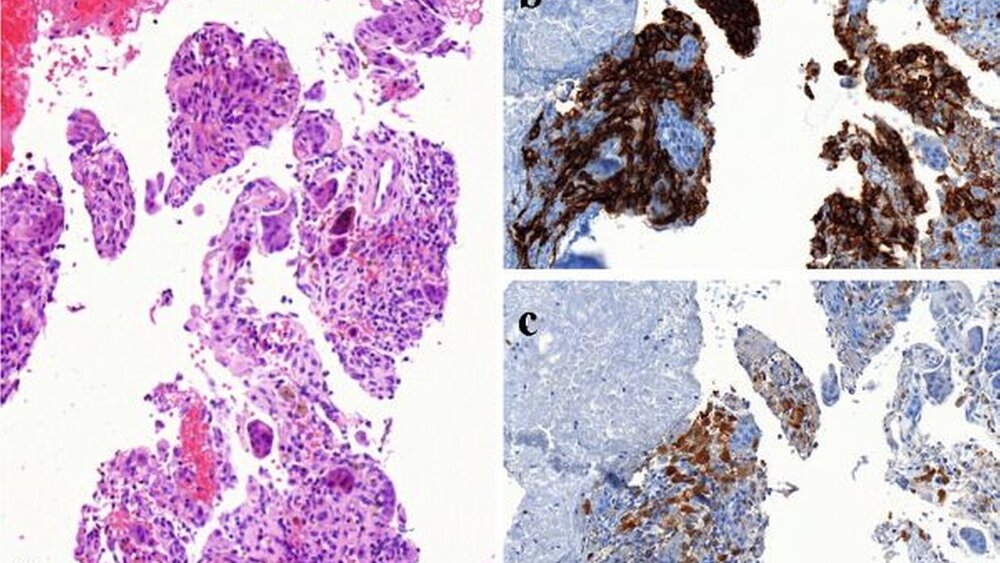

Die in Intubationsnarkose durchgeführte Biopsie der Raumforderung ergab bei der histopathologischen Untersuchung kortikospongiöses Gewebe mit Zeichen reaktiver Knochenbildung sowie eine zellreiche, riesenzellhaltige Proliferation. Insgesamt war dieser Befund in Korrelation mit der radiologischen Bildgebung gut mit einer aneurysmatischen Knochenzyste vereinbar. In Vollnarkose erfolgte nun die operative Exkochleation und Kürettage der zystischen Struktur unter Schonung des Nervus alveolaris inferior (Abbildung 3). Das zur histopathologischen Untersuchung eingesandte Gewebe ergab nach referenzpathologischer Mitbeurteilung in Abweichung zum Vorbefund die Diagnose einer Langerhans-Zell-Histiozytose. Hinweisend für diesen Befund war im vorliegenden Fall die in den histologischen Schnitten erkennbare immunhistochemische Koexpression von S100 und CD1a (Abbildung 4).

Die sichere Diagnosestellung einer Lan- gerhans-Zell-Histiozytose beruht auf der histopathologischen Untersuchung einer entnommenen Gewebsbiopsie. Charakteristisch hierbei sind der elektronenoptische Nachweis von sogenannten Birbeck-Granula und der immunhistochemische Nachweis von CD1a-Antigen auf der Zellober fläche, S-100 und Vimentin. Morphologisch zeigen sich in der konventionellen Lichtmikroskopie die typischen Langerhans-Zellen, wobei die Anzahl mit dem Alter der Läsionen variiert [Henry, 2005].

Differenzialdiagnostisch kam bei unserem kleinen Patienten zunächst eine entzündliche Genese der Schwellung in Betracht. Die klinische Untersuchung sowie die konventionelle Röntgendiagnostik schlossen einen odontogenen Fokus aus. Die für die in der radiologischen Bildgebung nachgewiesenen Osteolysen ebenfalls infrage kommenden Prozesse wie Zysten, aber auch benigne oder maligne Tumore (zum Beispiel Osteosarkom, Ewing-Sarkom) konnten histopathologisch ausgeschlossen werden. Insbesondere die Unterscheidung zur aneurysmatischen Knochenzyste bereitete in diesem Fall dem Pathologen aufgrund des Gehalts an osteoklastären Riesenzellen und der septalen Gewebskonfiguration Schwierigkeiten (Abbildung 4), konnte schließlich jedoch nach den entsprechenden immunhistochemischen Untersuchungen abgegrenzt werden [Henry, 2005; Jundt, 2005].